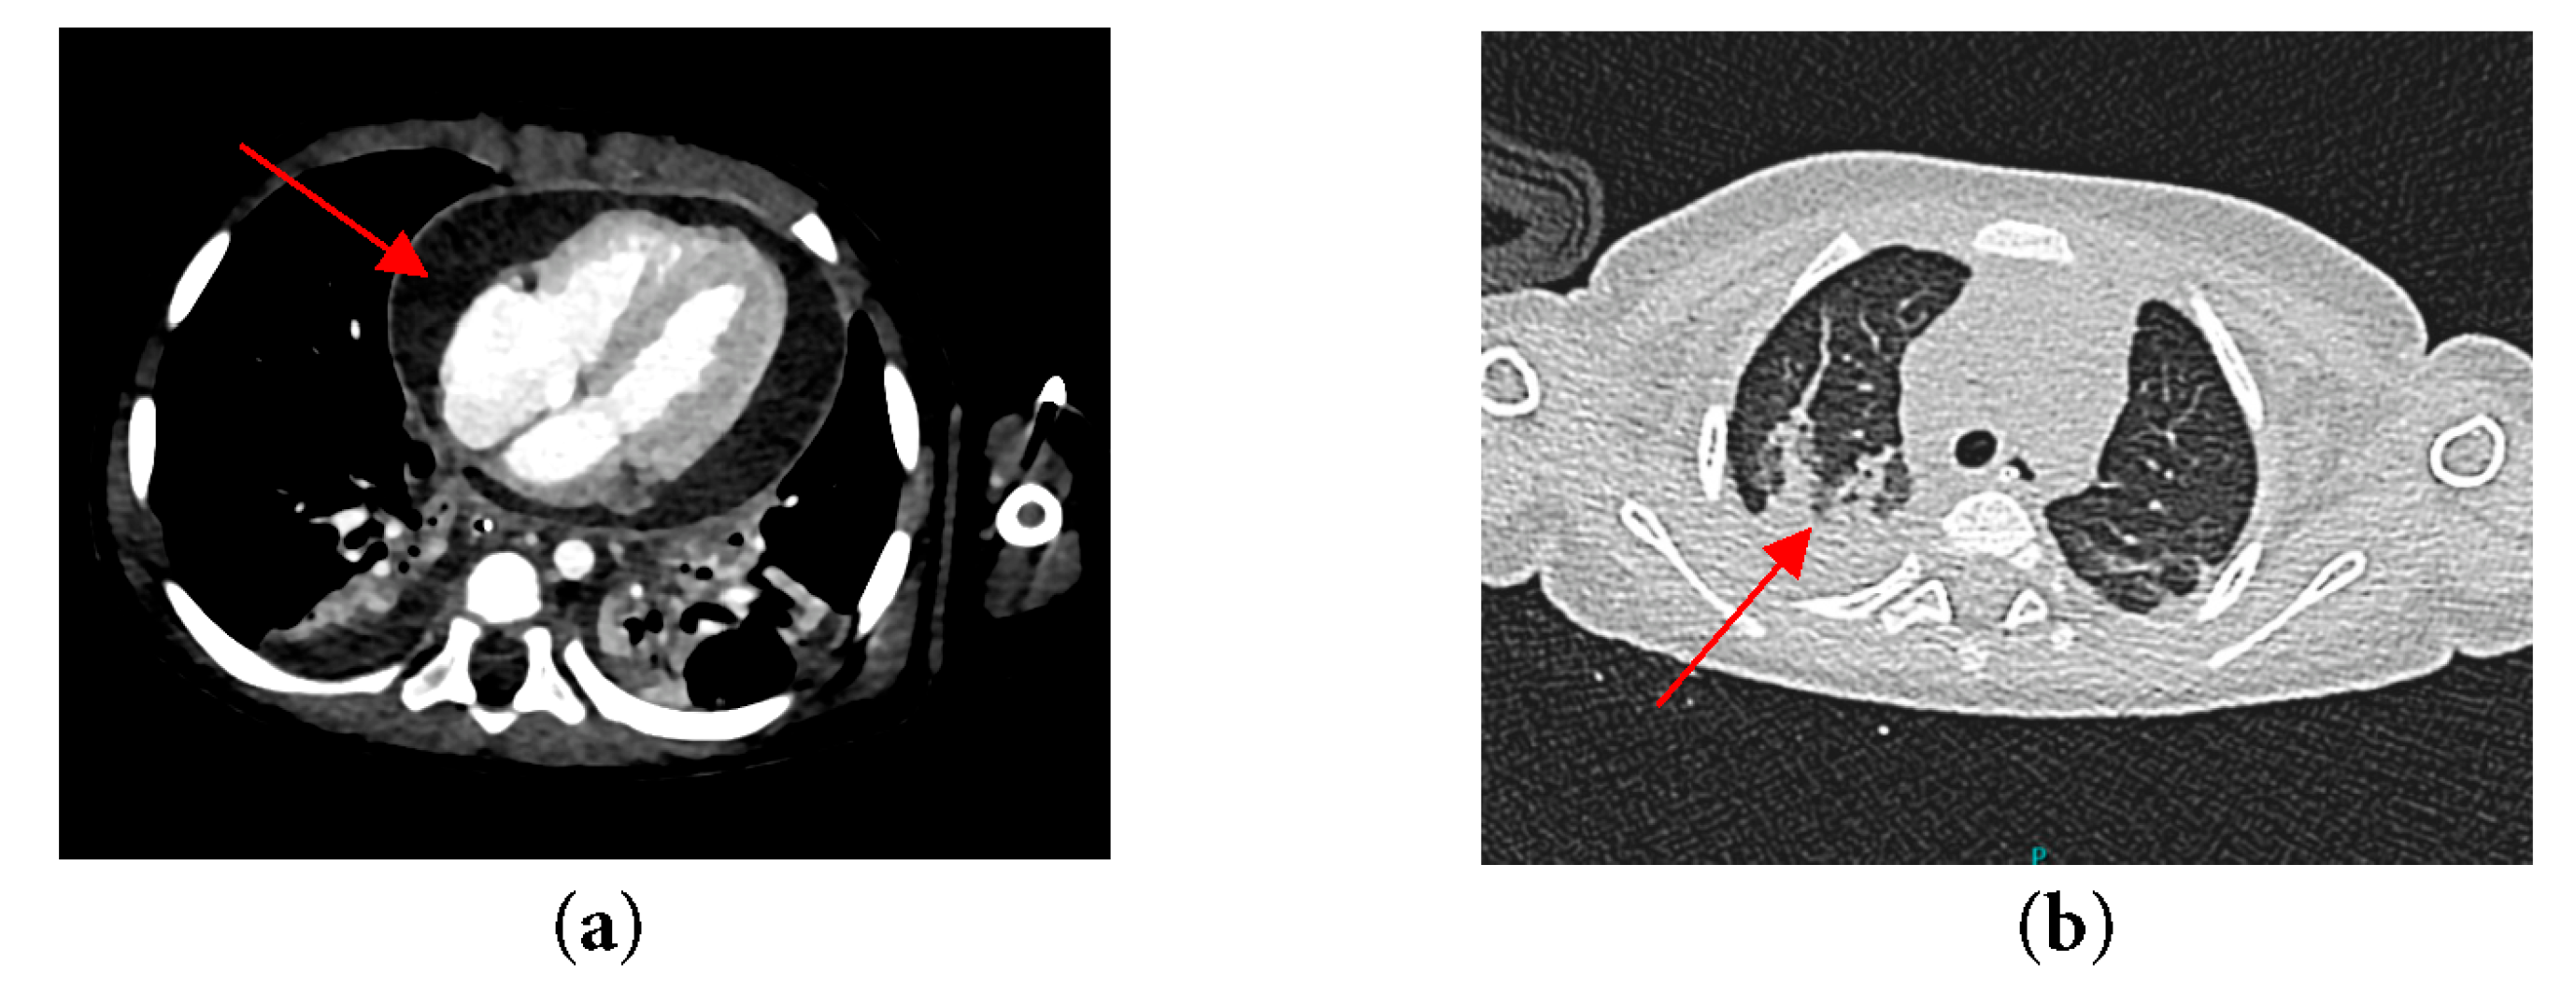

In anticipation of urgent surgical intervention for pericardial washout due to constrictive pericarditis, and to prevent cardiovascular collapse during transfer, the patient was electively intubated. Following intubation, a chest radiograph was performed, which demonstrated significant cardiomegaly with an endotracheal tube (ETT) seen in situ (Fig. 2). Computed tomography (CT) of thorax, abdomen and brain was also done and revealed bilateral pleural effusion with segmental collapse consolidation of both lower lobes. Pericardial effusion was seen and multiple mediastinal lymphadenopathy is identified, measuring 0.8 cm. Otherwise, no focal lesion such as space occupying lesions (SOL) was seen (Fig. 3).

Figure 3: CT thorax of the patient revealing (a) Constrictive pericardial effusion; (b) Segmental collapse consolidation of both lower lobes.

A month later, she came back for a post-pericardiectomy follow-up and assessment, echocardiogram noted a left atrial aneurysm as well as moderate to severe mitral regurgitation (Fig. 4a). Computed Tomography angiography (CTA) was done to assess the extension of the aneurysm and revealed a large left atrial aneurysm measuring 4.5 mm × 29.2 mm × 26.5 mm in size (Fig. 4b).

Figure 4: (a) Left apical four chamber echocardiographic view with color Doppler demonstrating a large intrapericardial left atrial aneurysm (b) CTA of patient’s heart demonstrating a left atrial aneurysm.